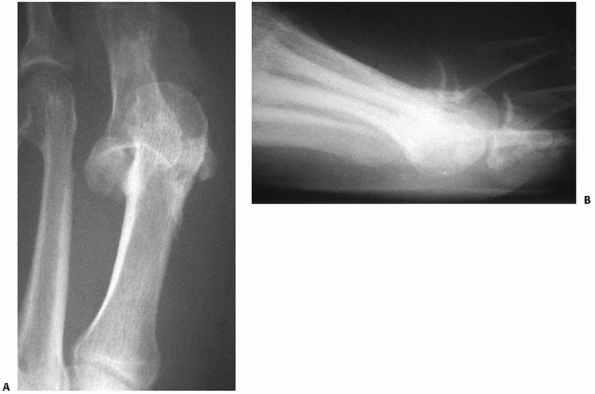

strength of individual ligaments across many of these joints. The

important characteristics to note are (a) the plantar ligaments are

significantly stronger than the dorsal ligaments, (b) the multiple

ligaments overlap among the joints of the lesser four tarsometatarsal

joints, and (c) the Lisfranc ligament, which is the largest and

strongest ligament of this joint complex, represents the only

ligamentous support between the medial leg and the middle and lateral

legs in the forefoot. The Lisfranc ligament originates from the plantar

lateral aspect of the medial cuneiform just below the plantar extent of

the second tarsometatarsal joint and inserts on the plantar and medial

aspect of the second metatarsal base. At best it is an indirect link

between the first and second metatarsals. There is no interligamentous

connection between the first and second metatarsal.

are important for management are stability and associated fracture

management. Extra-articular fractures, which appear with these

injuries, should be treated as described elsewhere in this text to

preserve that structure’s role in foot function. Intra-articular

fractures of the tarsometatarsal joints should be handled in the

context of the treatment of the joint complex.

with metatarsal motion, and tenderness to palpation but fail to exhibit

any instability should be considered a sprain. In addition to the

normal concept of rest, ice, compression, and elevation (RICE) for

treating sprains, the need for immobilization is important. These

injuries can be severely debilitating and require a long recovery

period.24,76

Nondisplaced ligamentous injuries with or without small plantar

avulsion fractures of the metatarsal or tarsal bones should be placed

in a well-molded short-leg walking cast (Table 60-5).

Initially, the patient is kept non-weight bearing with crutches and

only permitted to bear weight as comfort allows. Once full weight

bearing can be accomplished in a cast, the patient is tested for